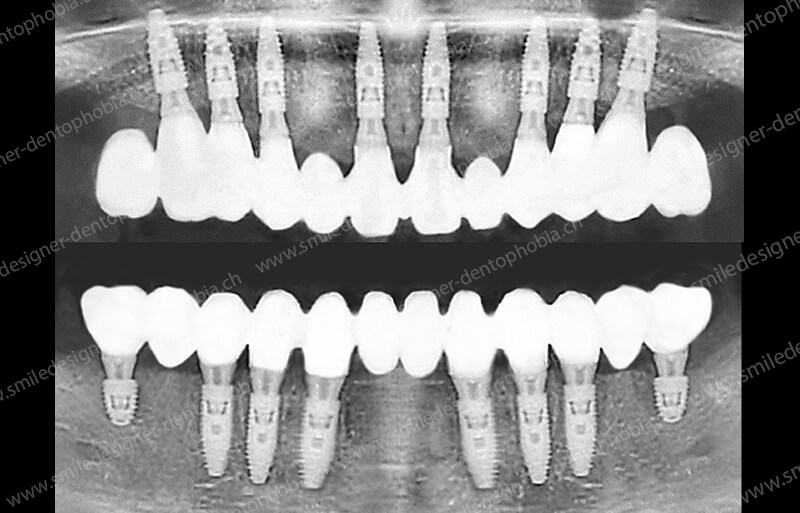

Cas clinique « GOLD DAMAGE CONTROL MCI » maxillaire : Bridge implanto-porté avec extensions postérieures (ALL ON 8). Version définitive des bridges avec un cosmétique en céramique.

Cas clinique « GOLD DAMAGE CONTROL MCI » maxillaire : Bridge implanto-porté avec extensions postérieures (ALL ON 10). Version définitive des bridges avec un cosmétique en céramique.

- Sans greffe osseuse pré-implantaire : même en cas de résorption osseuse importante, le protocole optimise la pose d’implants (jusqu’à 10 au maxillaire et 8 à la mandibule) pour soutenir des bridges esthétiques, avec des extensions postérieures pour une mastication complète.

- Résultat immédiat : dès la chirurgie, des bridges provisoires en composite sont posés, suivis de restaurations définitives en céramique après 6 à 12 mois de cicatrisation.